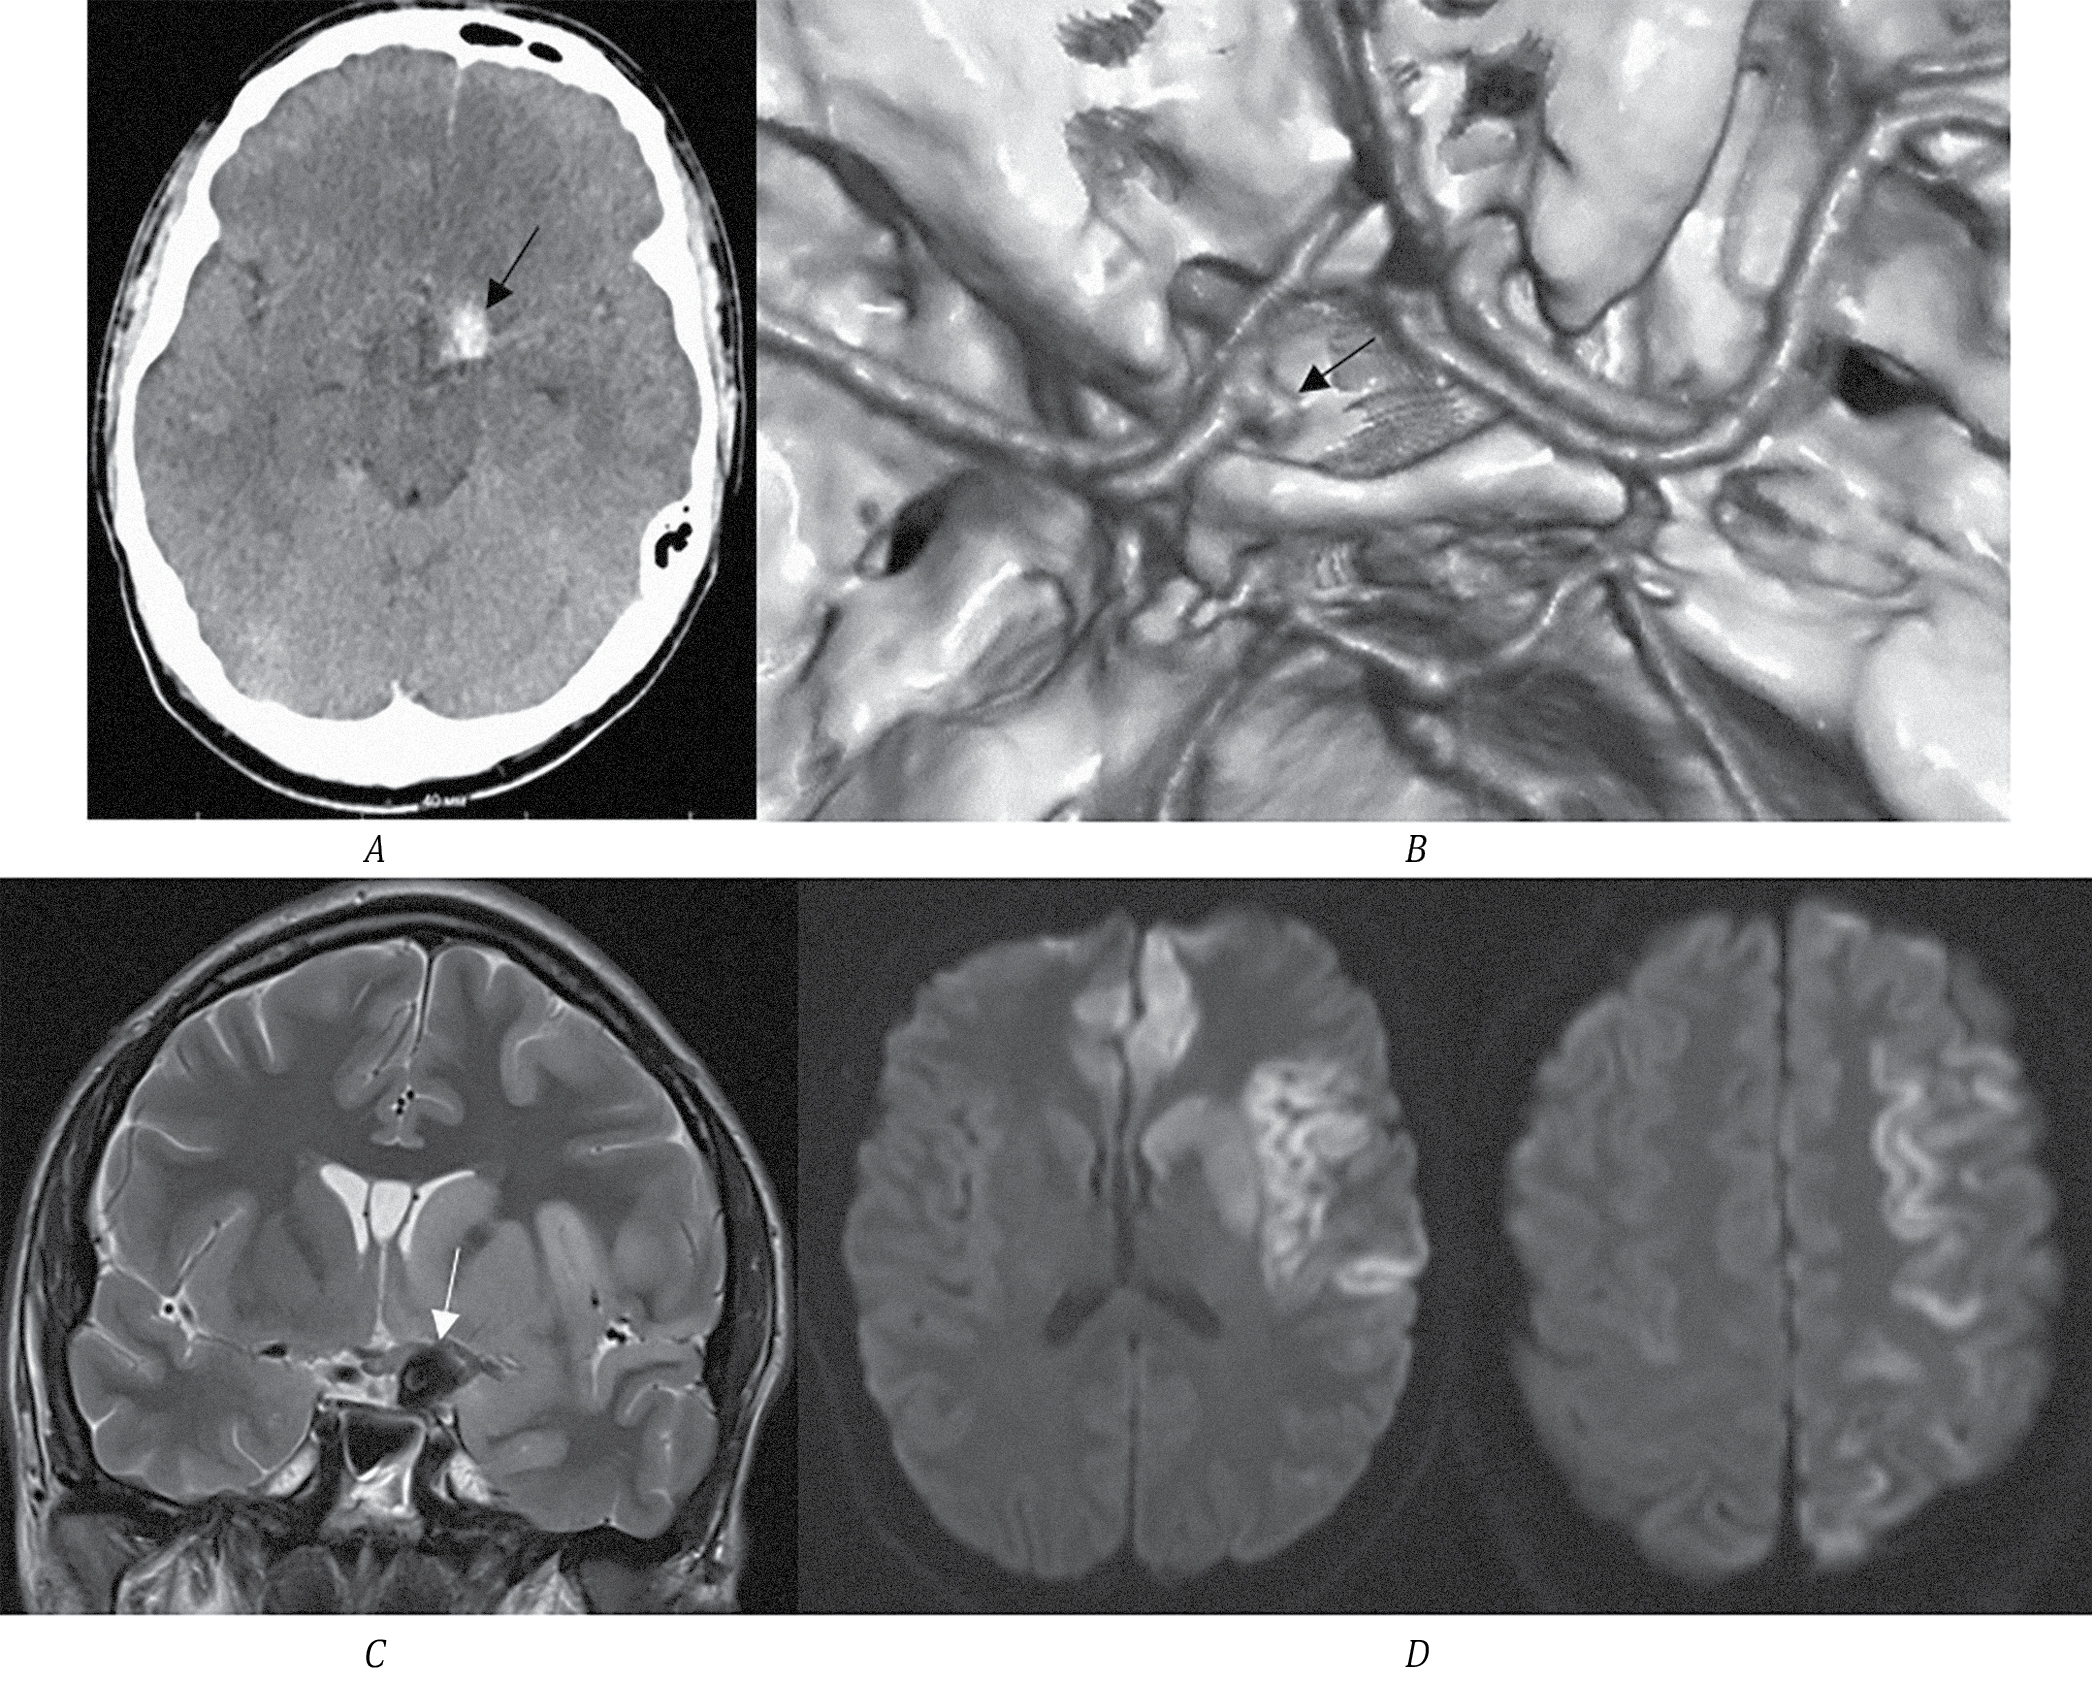

В приёмный покой доставлен пациент А., 24 года, с остро развившейся правосторонней гемиплегией. Выполнено МСКТ головного мозга: выявлен участок повышенной плотности в хиазмально-селлярной области слева, который необходимо дифференцировать как очаг кровоизлияния или ТА ВСА (рис. 4, А). По МСКТ-ангиографии определяется небольшая функционирующая часть аневризмы левой ВСА. ВСА и СМА слева проходимы на всём протяжении.

Рис. 4. МСКТ головного мозга пациента А.

А — стрелкой указана ТА левой ВСА; B — МСКТ-ангиография, 3D-реконструкция, стрелкой указана функционирующая часть аневризмы левой ВСА; C — МРТ головного мозга, Т1-ВИ, стрелкой указана ТА левой ВСА; D — МРТ в режиме DWI, зоны острой ишемии — в подкорковых структурах левого полушария головного мозга.

Выполнено МРТ головного мозга. Определяется ТА левой ВСА размером 15 мм. В режиме DWI определяются зоны острой ишемии (ограничения диффузии) в области головки хвостатого ядра справа, скорлупы, коры островка, латеральных и медиальных отделов правой лобной доли. С учётом такого многоочагового характера ишемии и наличия ТА ВСА наиболее вероятно, что эмболия из мешка тромбов привела к формированию множественных зон ишемии. Других факторов риска ИИ у молодого пациента не выявлено. Неврологический статус пациента оценён в 11 баллов по NIHSS. В плановом порядке выполнено микрохирургическое клипирование аневризмы ВСА. Пациент выписан с функциональным статусом на уровне 2 по модифицированной шкале Рэнкина.